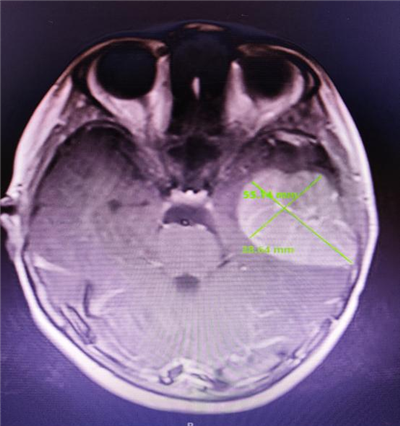

术后

为了确保患儿手术顺利进行,将手术风险降到最低,从术前方案设计、手术准备到术中风险把控,以及术后围手术期管理,张洪钿教授与神经外科团队通力合作,安全保障每个细节。术中,护士长陈婷婷全程陪同,手术在显微镜下进行了肿瘤切除术。术中的每一步操作都小心谨慎,历时三个小时的奋战,肿瘤被完整切除,患儿顺利返回病房。

术后经过十天的悉心护理,患儿的眨眼症状几乎消失,且未出现任何并发症,家人也终于把悬着的心放了下来,小强最终顺利出院回家。